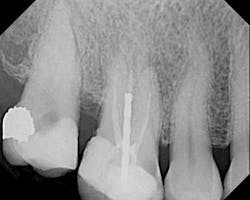

The female patient whose radiographic image appears in Figure 1 presented with a clinical history that is instructive with regard to endodontic diagnosis, treatment planning, and emergency management.

The patient said that the root canal in No. 3 was performed nine years ago. Approximately one month before she came to my office, she had increasing pain in the upper right that her general practitioner diagnosed as irreversible pulpitis in No. 2. Access was made at that time. The patient continued to have pain that became localized to No. 3. She also reported that the pulpotomy for No. 2 took approximately three hours and that the dentist had also seen other patients during the process. The patient found another general dentist who referred her to me.

Among other findings, No. 3 was sensitive to percussion and palpation. The tooth was not mobile and probing was approximately a six at the distal. The tooth had never been crowned. There was significant uncleaned and unfilled space in the root canal system, especially in the palatal and mesiobuccal roots. Recurrent decay was present at the mesial.

No. 2 had an access made through the occlusal and no discernable canals were visible in this or any of the radiographic angles. No. 2 was asymptomatic upon my examination. The patient’s medical history was noncontributory.